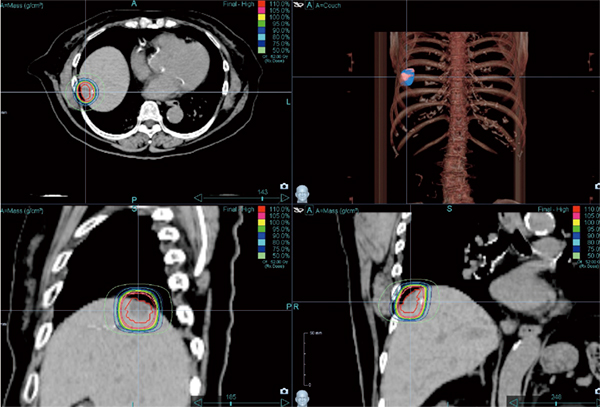

図1 直腸がん肝転移に対する Synchrony-SBRT症例

上段は図1の症例で,Synchronyを用いた直腸がん肝転移の症例。下段は肺がん肝転移に対してITV法で行った症例。肝転移自体の大きさはほぼ同じで,上段の直腸がん肝転移の方が線量が高いにもかかわらず,周囲の正常肝の変化は小さい。Synchronyでの治療により,周囲肝組織へのダメージがかなり抑えられているのがわかる。